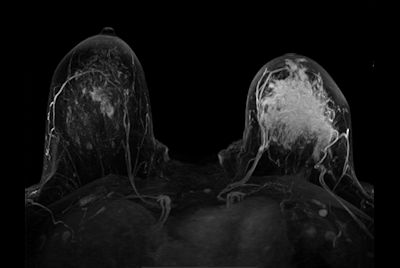

Breast biopsy with dS Sentinelle Breast coil

-

Dynamic Breast imaging with SmartSpeed AI

-